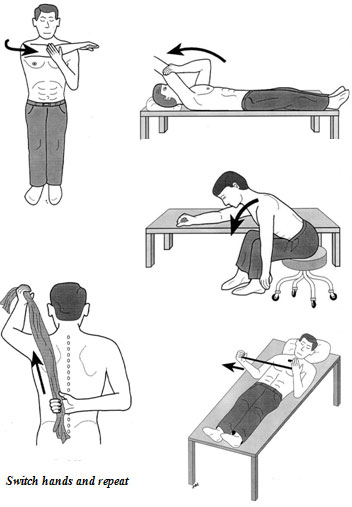

Treatment starts with physical therapy (range of motion exercises). This is the mainstay or the gold standard in all frozen shoulder conditions. Physical therapy ensures that the patient will continue to move the joint despite having a painful shoulder. This is particularly important in the second stage of this condition where the stiffness will be at its maximum and even though the pain is subsiding. Passive stretching of the joint in all directions using the opposite limb is done 3-4 times a day, every day. Assistive devices such as a towel, table or wall, and a broom- or walking-stick could also be used to provide maximum effect (see picture).